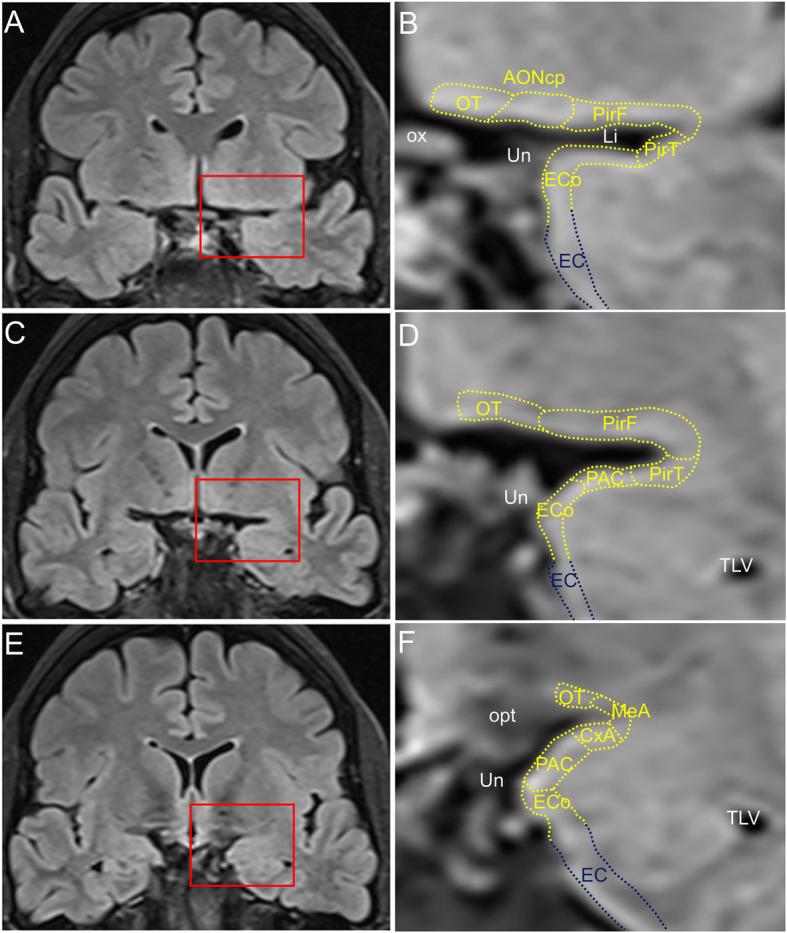

Alzheimer's and Parkinson's diseases are the most prevalent neurodegenerative disorders. Their etiologies are idiopathic, and treatments are symptomatic and orientated towards cognitive or motor deficits. Neuropathologically, both are proteinopathies with pathological aggregates (plaques of amyloid-β peptide and neurofibrillary tangles of tau protein in Alzheimer's disease, and Lewy bodies mostly composed of α-synuclein in Parkinson's disease). These deposits appear in the nervous system in a predictable and accumulative sequence with six neuropathological stages. Both disorders present a long prodromal period, characterized by preclinical signs including hyposmia. Interestingly, the olfactory system, particularly the anterior olfactory nucleus, is initially and preferentially affected by the pathology. Cerebral atrophy revealed by magnetic resonance imaging must be complemented by histological analyses to ascertain whether neuronal and/or glial loss or neuropil remodeling are responsible for volumetric changes. It has been proposed that these proteinopathies could act in a prion-like manner in which a misfolded protein would be able to force native proteins into pathogenic folding (seeding), which then propagates through neurons and glia (spreading). Existing data have been examined to establish why some neuronal populations are vulnerable while others are resistant to pathology and to what extent glia prevent and/or facilitate proteinopathy spreading. Connectomic approaches reveal a number of hubs in the olfactory system (anterior olfactory nucleus, olfactory entorhinal cortex and cortical amygdala) that are key interconnectors with the main hubs (the entorhinal-hippocampal-cortical and amygdala-dorsal motor vagal nucleus) of network dysfunction in Alzheimer's and Parkinson's diseases.